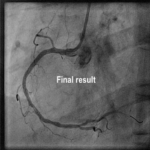

India’s First Transradial Rotablation with Rotapro Device for LMS PCI (25 April 2022)

India’s first successful LMS rotablation using the Rotapro device through the transradial route.